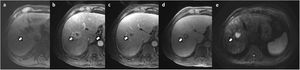

In the investigation of liver metastases from neuroendocrine tumours, the combination of HBP and the diffusion sequence also had the highest detection rate compared to the rest of the sequence combinations and showed sensitivity and specificity of 86% and 94% respectively.46 In the same study, this combination was statistically significant in showing the highest interobserver agreement. Another study showed that the HBP sequence had the highest contrast/noise ratio for the detection of liver metastases from neuroendocrine tumours.47 These studies suggest using hepatobiliary contrasts in the assessment of patients with suspected metastasis from neuroendocrine tumours (Fig. 9).

Patient with liver metastasis from ileal neuroendocrine tumour. Dynamic liver MRI with Gd-BOPTA (a–f): a) non-contrast phase; (b) arterial phase; (c) portal phase; (d) hepatobiliary phase; (e) T2-WI; (f) diffusion with b = 800); and PET/CT with Ga-68-DOTATATE (g). The lesion is hypervascular during the arterial phase (b), barely visualised during the portal phase (c), and is markedly hypointense in HBP (d), as well as hyperintense in the diffusion sequence (f). The PET/CT confirmed the presence of somatostatin receptors in the lesion (g).